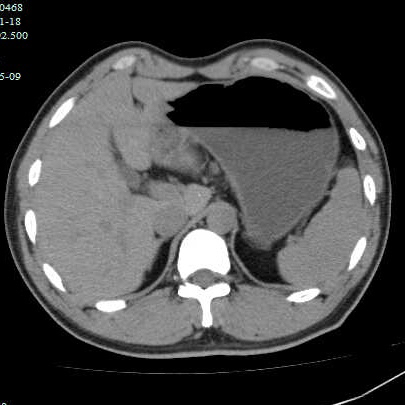

第二个病例,青年男性,也是突然腹痛,症状和第一个类似,首选腹部CT。

胃镜证实

同样治疗后痊愈出院

胃结石普遍以下特点:突然起病,以上腹痛及恶心、呕吐物为主要表现,胃镜是“金指标”,CT需结合临床